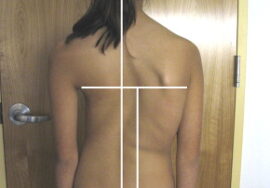

قد يلاحظ الأهل بعض العلامات البسيطة، مثل:

ميلان الكتفين أو عدم تساويهما

بروز أحد الضلوع أكثر من الآخر

ميلان الجسم إلى أحد الجانبين

اختلاف مستوى الخصر أو الظهر

الفحص السريري المنتظم: لملاحظة الميلان أو تغير مستوى الكتفين والخصر.